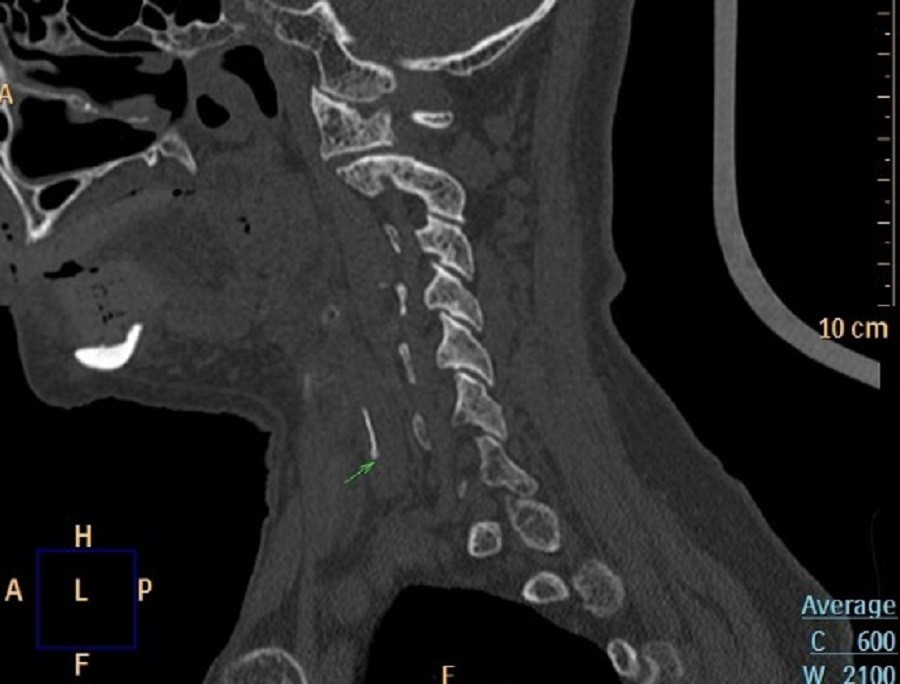

Khi được khám nội soi Tai Mũi Họng, bác sĩ phát hiện vùng sụn phễu trái phù nề nghiêm trọng. X‑quang cổ nghi ngờ có dị vật; CT xác định một mảnh xương cá dài khoảng 1,2 cm đã xuyên ra khỏi ống tiêu hóa và cắm sâu vào thùy trái tuyến giáp. Tình trạng này có nguy cơ gây nhiễm trùng, áp‑xè cổ và tổn thương các dây thần kinh quan trọng.

Đội ngũ y tế ba chuyên khoa (Tai Mũi Họng, Ngoại lồng ngực – mạch máu, Chẩn đoán hình ảnh) đã hội chẩn và quyết định phẫu thuật mở cổ để lấy dị vật. Bệnh nhân được điều trị đồng thời bằng kháng sinh, kháng viêm và thuốc giảm đau, giúp kiểm soát nhiễm trùng và giảm phù nề.